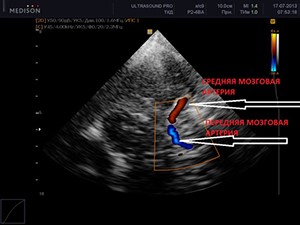

Допплерография – это дополнительная функция ультразвуковой диагностики, которая позволяет оценить характер и скорость тока крови в артериях и венах.

Если кровь движется по направлению к датчику, компьютер окрашивает ее красным цветом на изображении. Если в противоположную сторону, то синим.